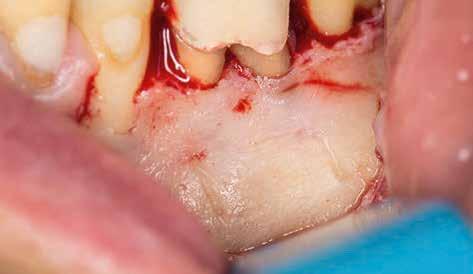

A beavatkozás során helyi érzéstelenítésben teljes vastagságú mucoperiostealis lebenyt képeztünk, és a sablon segítségével bejelöltük a preparálandó csontablak határait. Az ablak széleinek megfelelően Piezotome CUBE LED kézi-darabbal (ACTEON) a kortikális teljes vastagságában vágást ejtettünk, majd az így kapott csontlemezt (ablakot) eltávolítottuk (1. e–h. ábra), és ezt követően steril fiziológiás sóoldatba helyeztük. A rezekció elvégzését követően (1. i. ábra) a mezialis csatornákat ultrahangos eszközök segítségével (NSK) retrográd irányból preparáltuk, majd az így kialakított mélyedésbe retrográd gyökértömést készítettünk. A tömés anyagául az EndoSequence BC RRM Fast Set Putty-t (Brasseler) választottuk. A tömés elkészítését követően a csontablakot visszaillesztettük, és a stabilizálása érdekében a vágásoknak megfelelően kialakult résekbe kollagén szivacsokat (Collagen Tape, Zimmer Biomet) helyeztünk (1. j-k. ábra). A lebenyt 6/0-s Prolene varratokkal (Corpaul) rögzítettük.

A kétéves kontroll során elvégzett klinikai és radiológiai vizsgálat (CBCT-felvétel) a periapicalis elváltozások megszűnését és a corticalis csontállomány tünet- és szövődménymentes gyógyulását